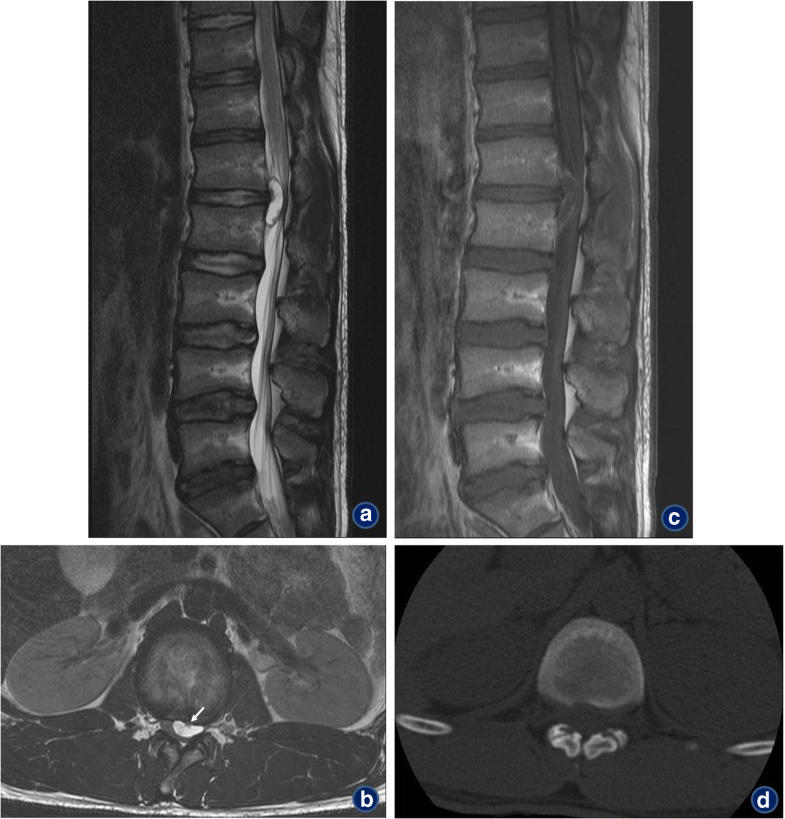

Lumbar spinal synovial cyst Image